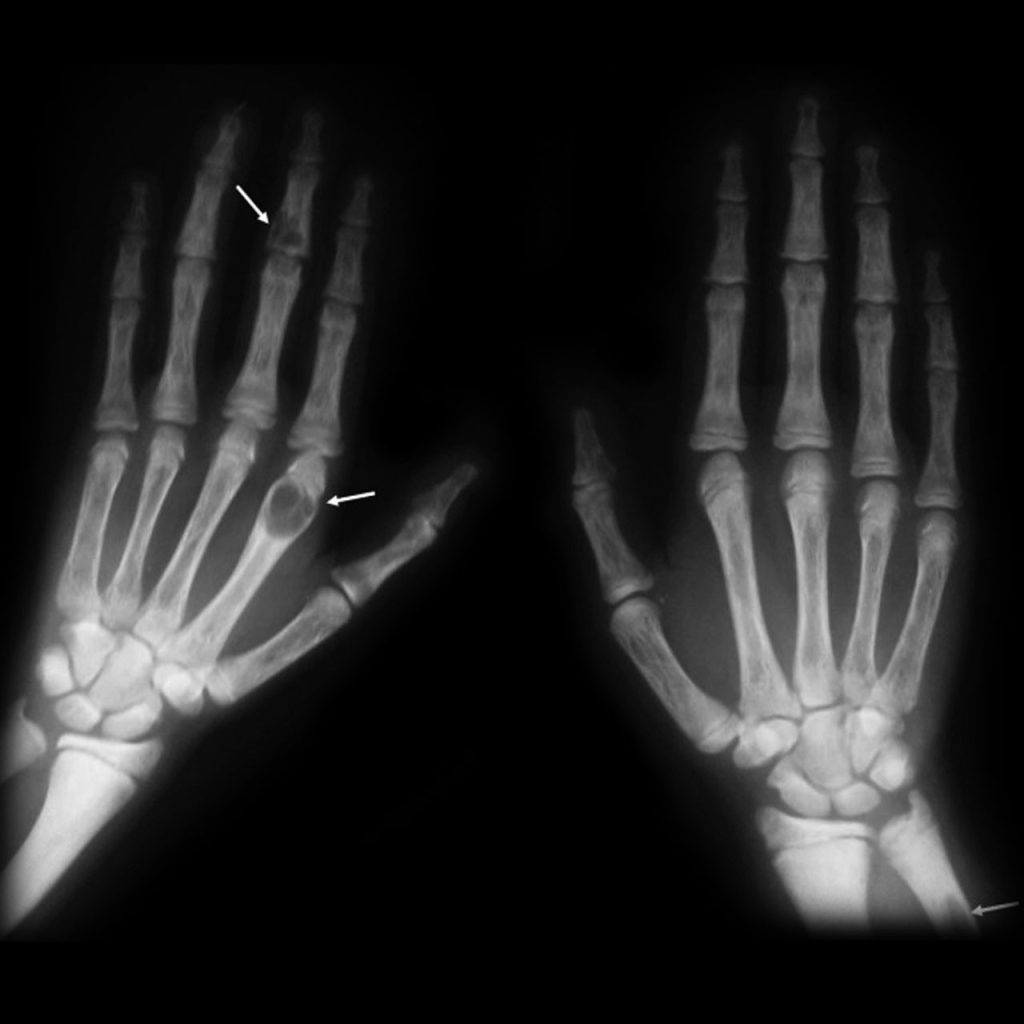

X-ray of two human hands showing bone structure; arrows point to potential abnormalities or lesions in the left hand's fingers and right hand's little finger.